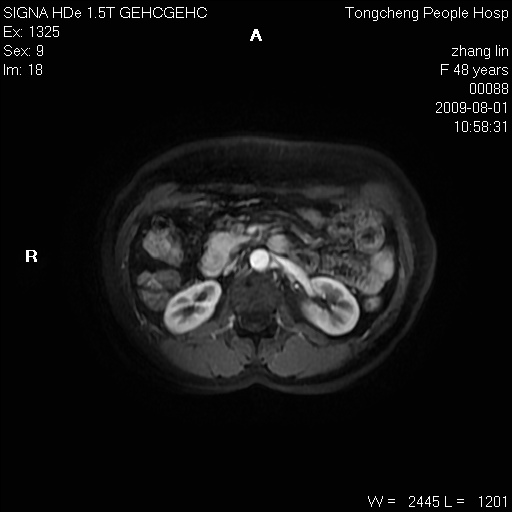

女,48岁。健康体检,彩超发现右肾占位性病变。平素健康。

临床诊断:右肾占位性病变,性质待定(囊肿?肿瘤?)。

上中腹部mr平扫+增强扫描,图像如下:

右肾上极见一类圆形病灶,t1wi呈等信号t2wi呈等高混杂信号,三期增强无强化,边界清---考虑囊肿出血。

同反相位均表现为等信号,病变无强化,考虑含蛋白的囊肿可能,弥散加权相或许有些帮助,

慢性胆囊炎